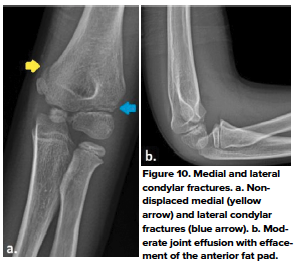

- Medial condylar fractures

- Medial condylar fractures are uncommon, accounting for less that 1% of all distal humeral fractures in children. These fractures usually occur in children 8-14 years of age after a fall onto an outstretched hand. Typically these fractures present with medial soft tissue swelling with pain in the condylar region. It is difficult to distinguish between these and medial epicondylar fractures, however, these usually are NOT related to dislocation.10 (Fig 10 a, b)